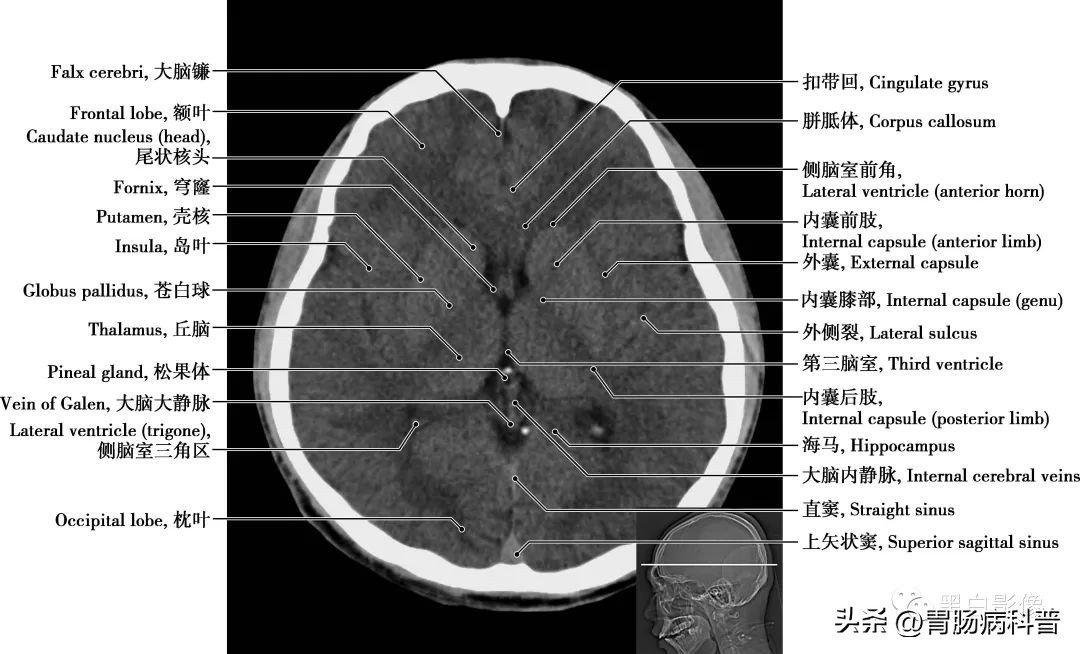

图1-1-9 经室间孔轴位切面

松果体 位于间脑脑前丘和丘脑间,为一豆状小体,其一端借细柄与第三脑室顶相连,第三脑室凸向柄内形成松果体隐窝。松果体通过分泌褪黑激素,影响和干预人类的许多神经活动,如睡眠与觉醒、情绪、智力等,还可合成多种肽类激素

图1-1-10 经第三脑室轴位切面

第三脑室 位于间脑中央,为两侧丘脑和下丘脑之间的矢状窄隙,前方借室间孔与侧脑室相通,后方与第四脑室相通。丘脑 为间脑最大的卵圆形灰质核团,位于第三脑室两侧,左、右丘脑借灰质团块相连,其被“丫”形白质板分成前、内侧和外侧三大核群。受损时,对侧偏身感觉减退,对侧动作性震颤或偏身共济失调伴舞蹈徐动症,情绪不稳等